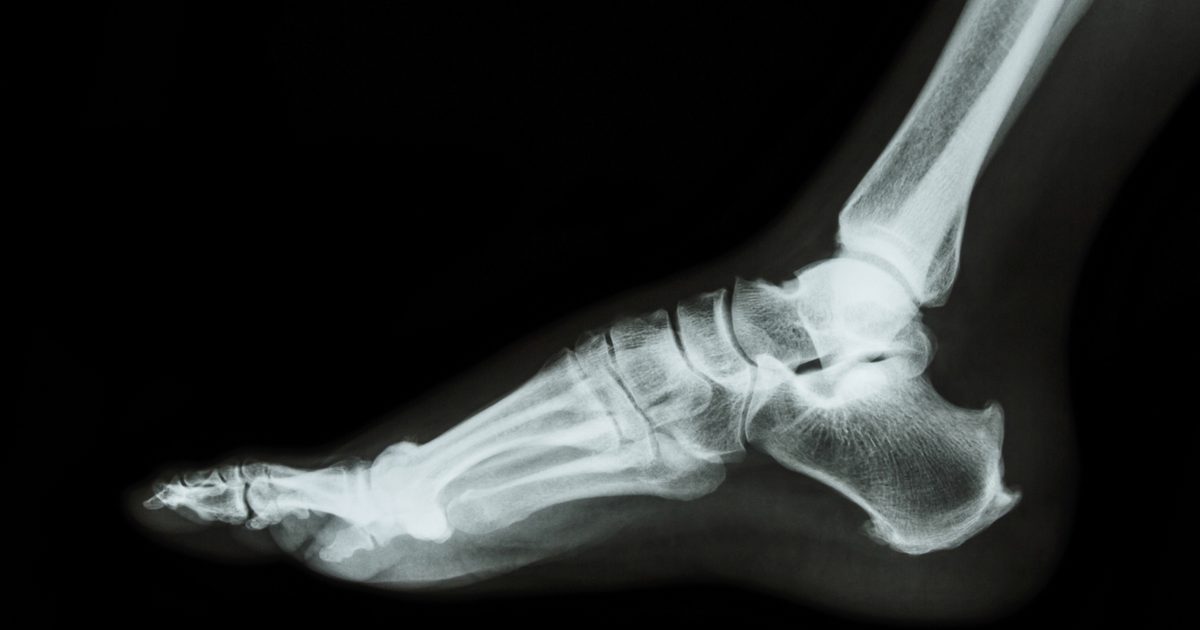

Magnetic Resonance Imaging And Ultrasound Testing

The two most common tests in diagnosing Morton's neuroma include magnetic resonance imaging (MRIs) and ultrasound testing. Your doctor is likely to recommend one to you during your visits. The conventional radiographs are likely not to provide accurate results or detect the condition accurately. You will require an x-ray examination, which uses sound waves in creating images of your foot.

MRIs and ultrasounds as testing are the most preferred because it provides accurate outcomes. The ultrasound method can help the physician distinguish Morton's neuroma from the others that may mimic the symptoms. The other likely complications are capsulitis, stress fractures, and plantar plate disruption. An MRI is another technique that provides an accurate diagnosis. The doctor will possibly see the neurovascular bundle region in the toe and determine the diagnosis.